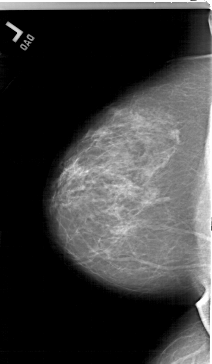

A_1515_1.LEFT_MLO

LEFT_MLO LINES 6466 PIXELS_PER_LINE 3586 BITS_PER_PIXEL 12 RESOLUTION 43.5 NON_OVERLAY